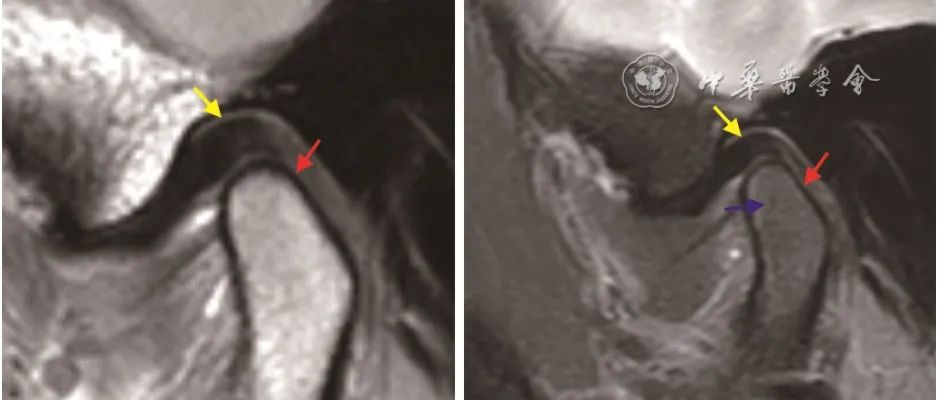

【继续教育园地】颞下颌关节骨关节炎的MRI成像诊断

点击“中华口腔医学杂志”快速关注本刊官微       作者:陈志晔 胡敏 王燕一通信作者:胡敏 王燕一作者单位:解放军总医院海南医院放射科(陈志晔);解放军总医院口腔颌面外科(胡敏);解放军总医院海南医院口腔科(王燕一)引用本文: 陈志晔, 胡敏, 王燕一. 颞下颌关节骨关节炎的MRI成像诊断[J]. 中华口腔医学杂志, 2022, 57(6): 660-664. DOI: 10.3760/cma.j.cn112144-20220113-00016....

中华口腔医 2022-06-16